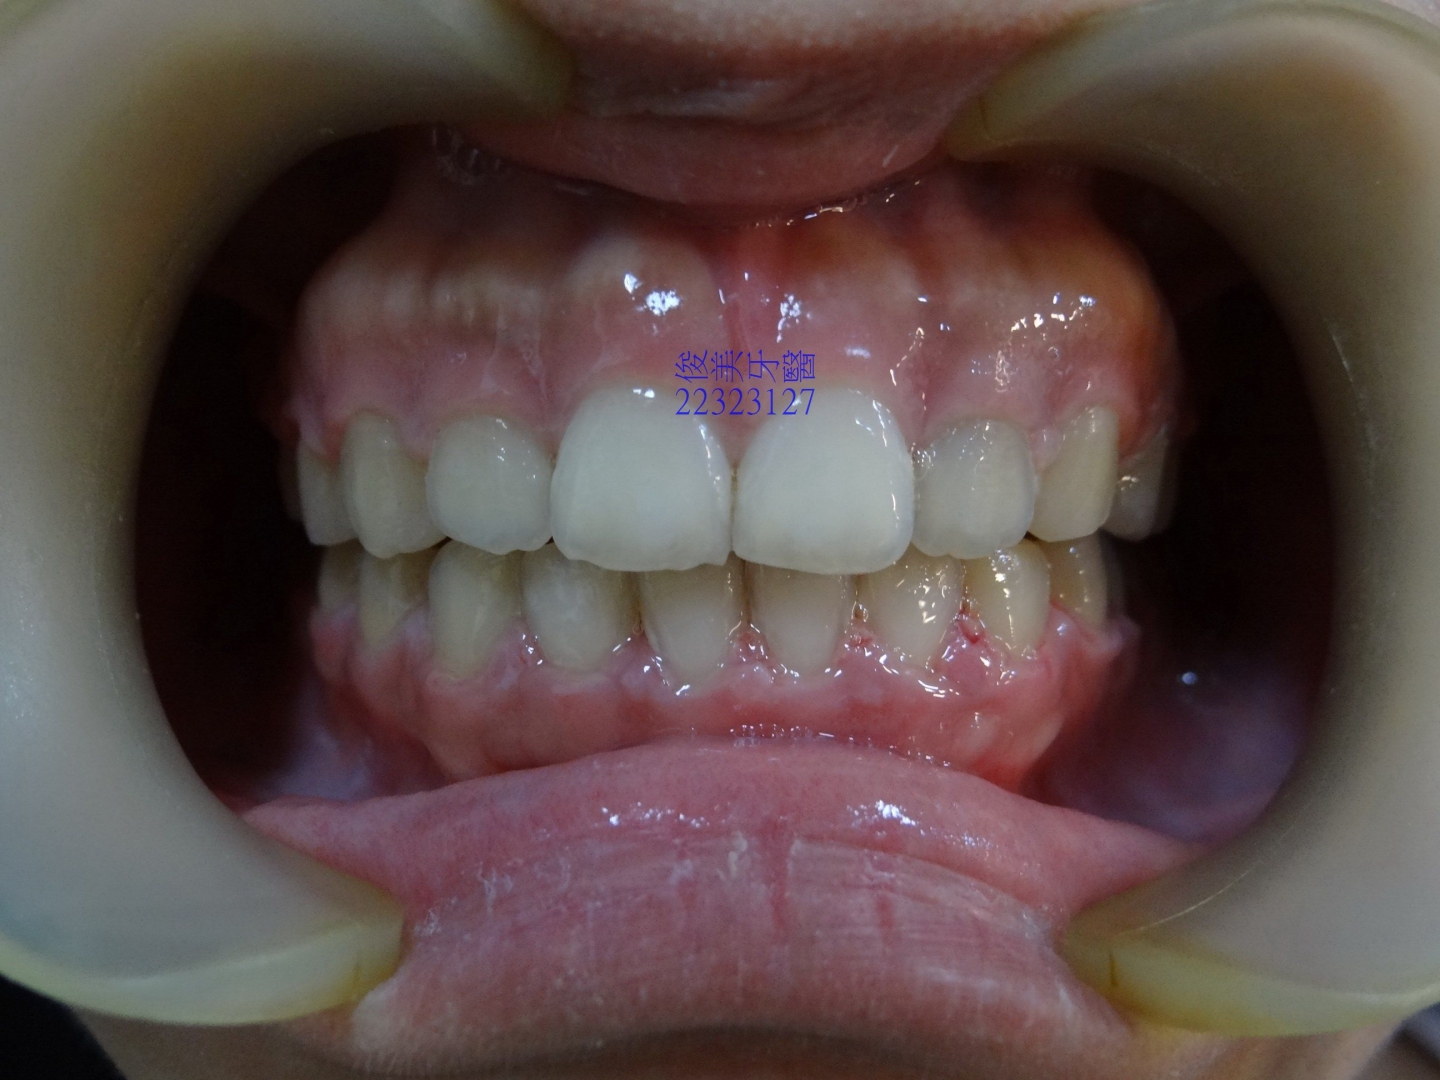

![]() 患者於門診中表示,牙齒很擁擠,想要改善;經醫師門診後,建議患者進行矯正治療即可改善。 ![]() 牙齒重疊... ![]() 有深咬現象... ![]() 上顎狀況... ![]() 下顎狀況... ![]() 左側咬合,牙齒往舌側傾斜...... . ![]() 右側咬合,牙齒往舌側傾斜...... ![]() 治療中....擁擠和深咬已改善.... ![]() 牙齒往後移.....將牙齒齒軸回正一點。 ![]() 治療結束,拆除矯正器了............. ![]() 患者好開心......牙齒整齊後,笑容更可愛了。 ![]() 也沒有暴牙的狀況。 ![]() 上顎牙弓狀況。 ![]() 下顎牙弓狀況。 ![]() 右側咬合狀況。 ![]() 左側咬合狀況。 ![]() 已拆除超過5年,依舊配戴維持器,保持最佳狀態。 |